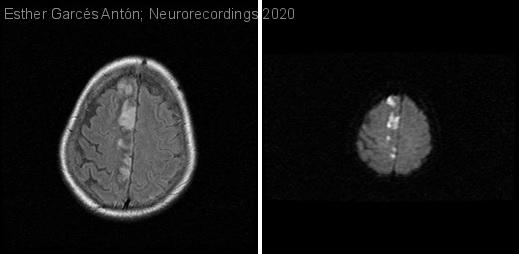

Diagnóstico final: Ictus isquémico de la arteria cerebral anterior derecha de etiología indeterminada

Mujer de 72 años con antecedentes de diabetes mellitus tipo 2 y dislipemia. No fumadora. Independiente para actividades de la vida diaria.